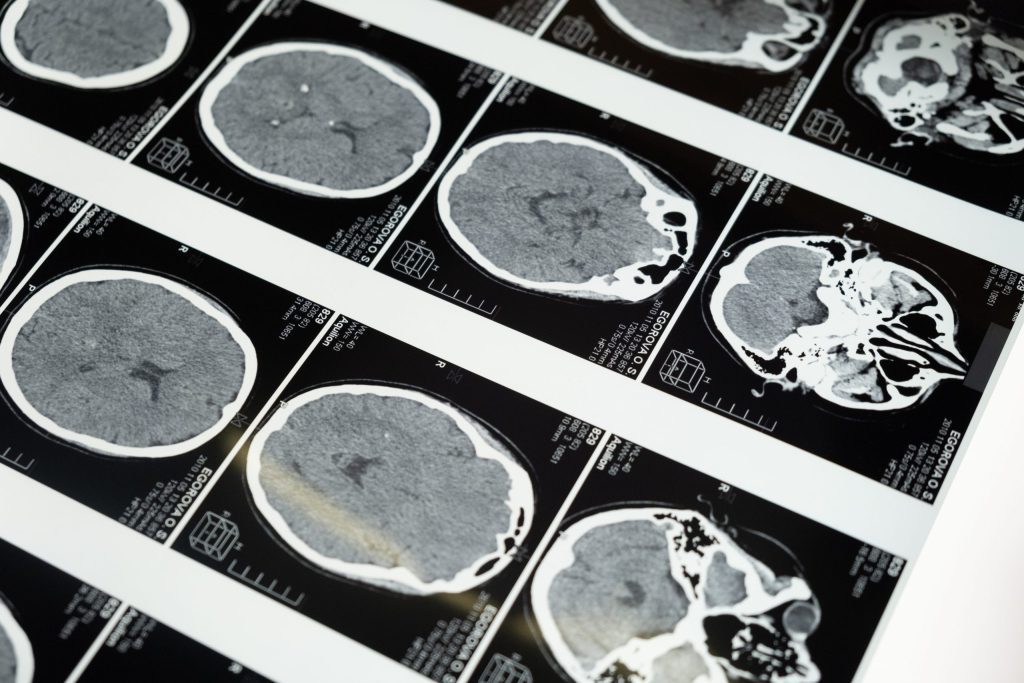

No todos los estados de desinhibición se deben a trastornos de salud mental, como el TLP. Por ejemplo, una lesión cerebral traumática puede provocar desinhibición. Ciertos medicamentos, como las benzodiacepinas, algunos medicamentos para dormir, las drogas de abuso y el alcohol, también pueden provocar desinhibición.